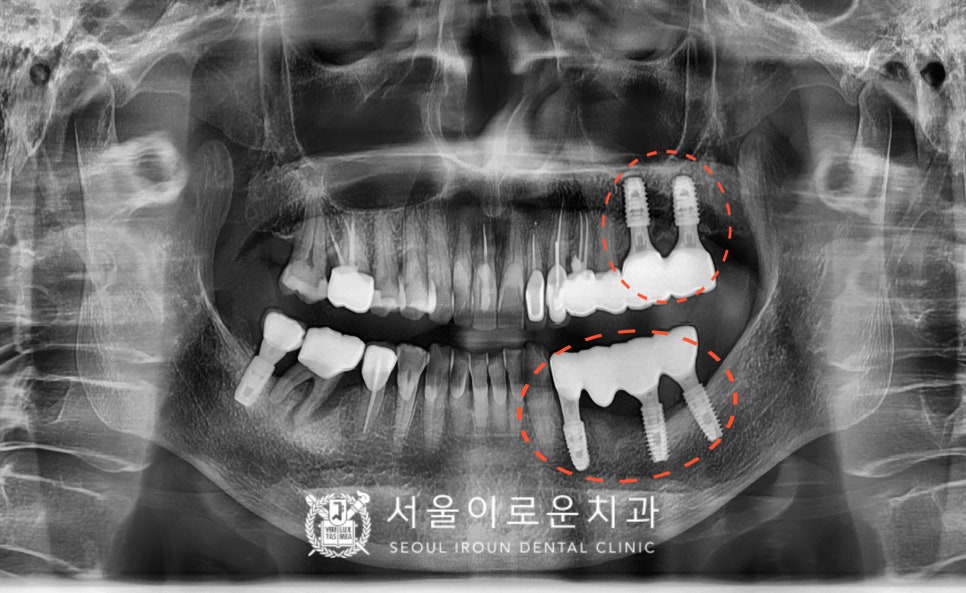

정밀한 검사를 위해

파노라마 사진을 촬영해 보았더니

✅ 불편감을 호소하셨던

빨간 동그라미 표시의

위턱 왼쪽 큰 어금니 두 개(#26,27)와

아래턱 왼쪽 첫 번째 작은 어금니(#34)는

치아 뿌리 끝까지 염증이 진행되어 있었으며

잇몸뼈가 녹아 동요도가 3도로

심하게 흔들리고 있고,

고름까지 나오고 있는 상태였는데요.

안타깝게도 이 경우에는

치아를 살려 쓸 수 없기 때문에

발치를 진행하기로 하였으며,

발치 후 염증조직을 깨끗하게 제거한 뒤

뼈이식을 동반한 임플란트 즉시 식립을

계획하였습니다.

더불어 타 치과에서 진행하셨던

아래턱 왼쪽 임플란트 주변으로는

임플란트 주위염이 관찰되었는데요.

✅ 특히 제일 앞쪽에 있는

주황색 화살표 표시의

아래턱 왼쪽 두 번째 작은 어금니(#35) 임플란트는

염증이 심한 상태라

임플란트 제거가 필요하였습니다.

✅ 보라색 화살표 표시의

아래턱 왼쪽 첫 번째 큰 어금니(#36)의 임플란트도

1/3 정도의 뼈 흡수 소견이 보이나

환.자분께서 유지관리하시길 원하시어

염증 제거 후 유지 관리하기로 했습니다.